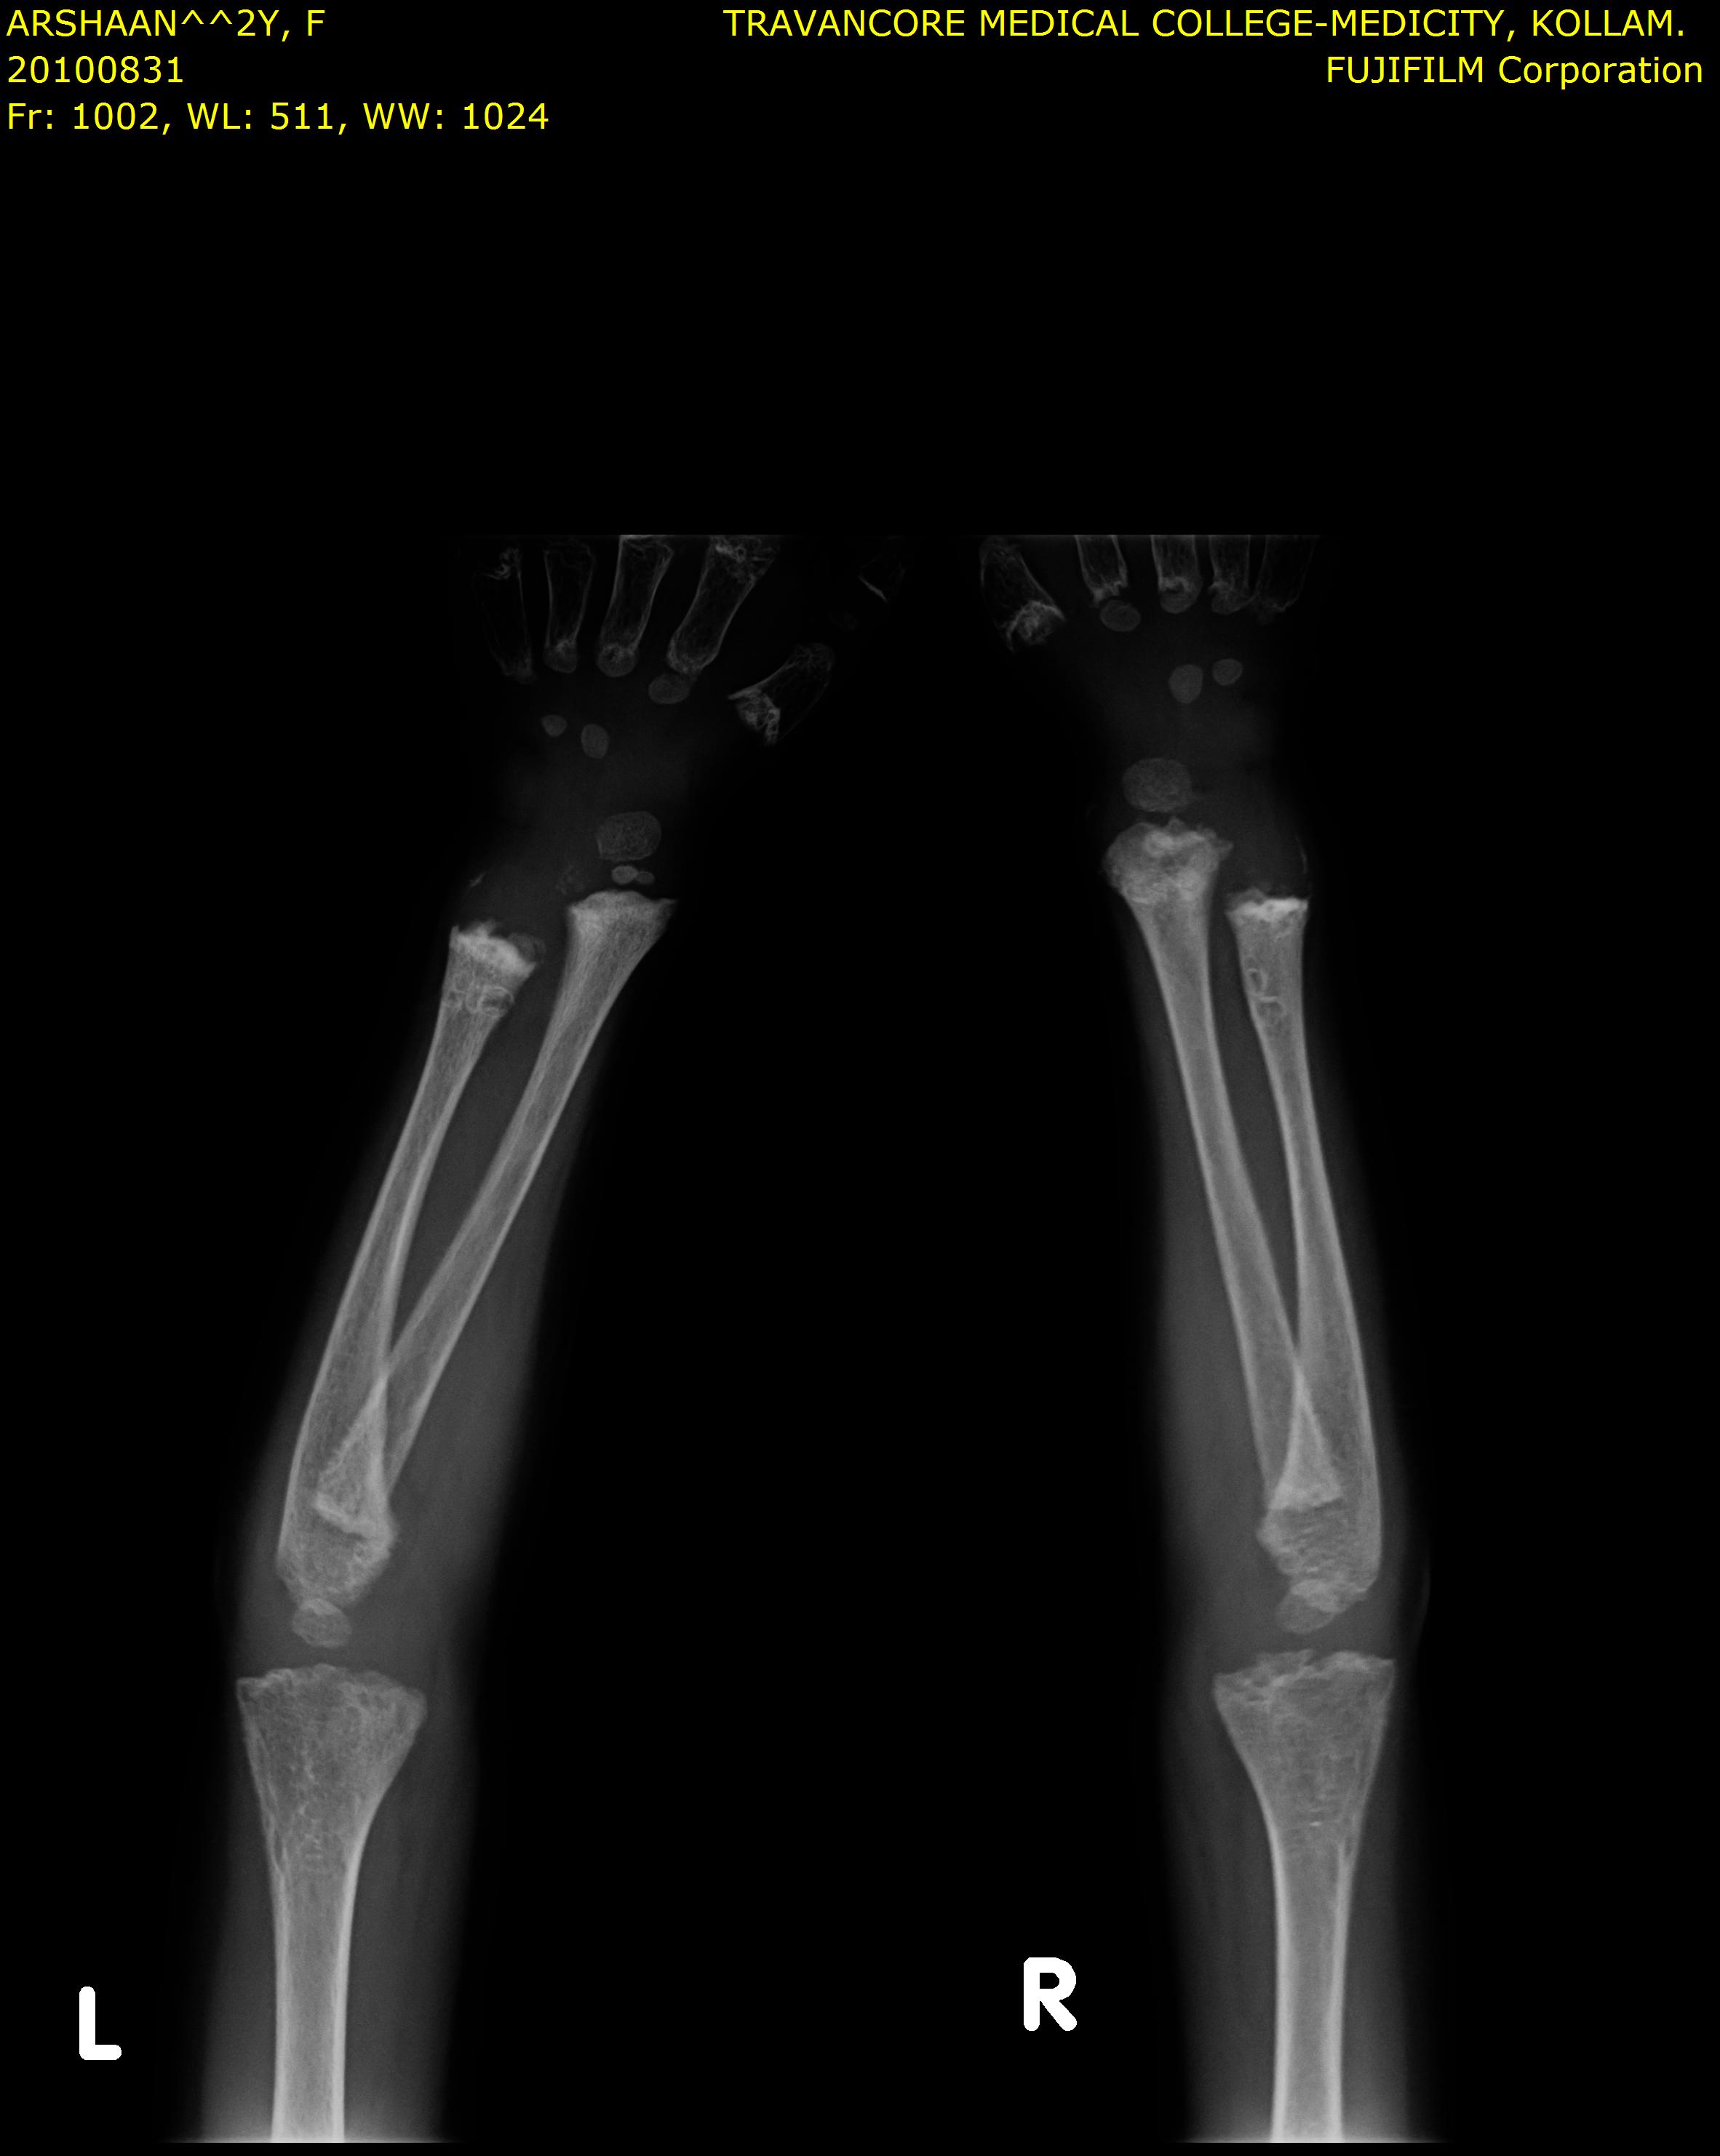

Here we share radiographic images to help with diagnosis of Jansen's disease:

Jansen's patients show extreme disorganization of the metaphyses of the long bones and of the metacarpal and metatarsal bones in sharp contrast to the almost normal appearance of the epiphyseal centers, which on x-ray appear widely separated from the long bones. The chin is receding. The fingers, especially the distal phalanges, are very short. The spine, pelvis, and lower legs are distorted.